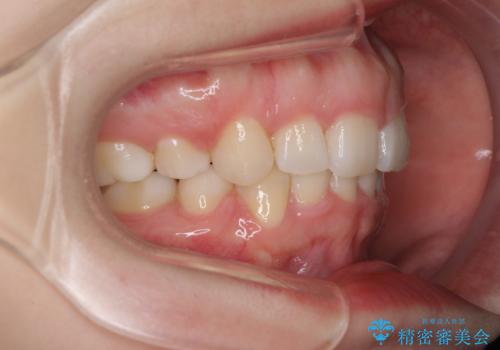

治療期間の目安は2年半~3年間でしたが、咬み合わせにより上顎装置が頻繁に脱落してしまい、治療期間が長期化してしまいました。

期間はかかったものの、口元の張り出し感や歯のデコボコが解消され、患者様には大変満足していただけました。